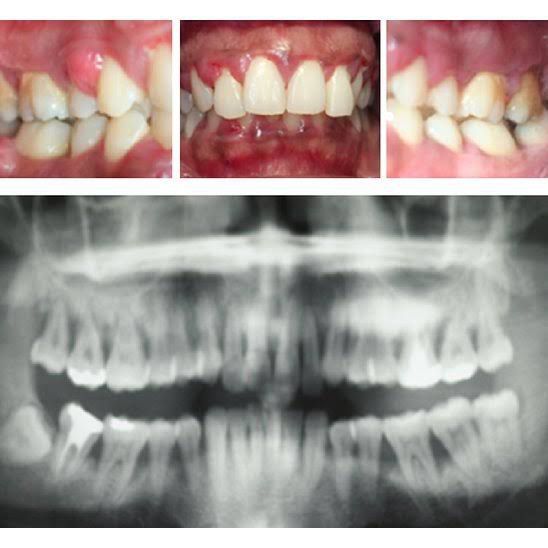

Aggressive periodontitis is a destructive disease characterized by the following: the involvement of multiple teeth with a distinctive pattern of periodontal tissue loss; a high rate of disease progression; an early age of onset; and the absence of systemic diseases.